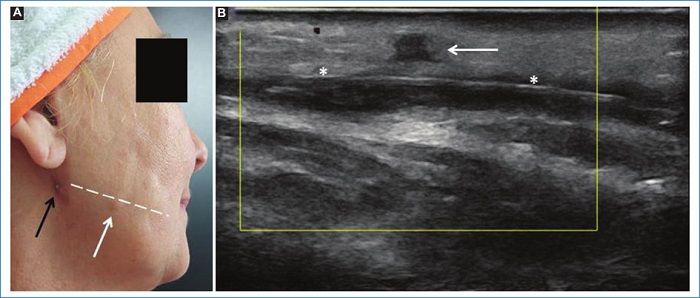

Del grupo 1 (n = 53, 63% del total de pacientes), 51 (96,2%) pacientes eran de sexo femenino y 2 (3,7%) de sexo masculino, 24 (45,2%) no presentaban rellenos previos, 15 (28,3%) presentaban ácido hialurónico (AH) y 14 (26,4%) tenían rellenos permanentes (biopolímeros, silicona y polimetilmetacrilato). Además, 12 (22,6%) pacientes de este grupo presentaron variantes anatómicas, de los cuales solo uno tenía un relleno previo de AH. Entre las variantes encontradas se mencionan arterias angulares, labiales, nasal dorsal y temporal profunda en sitios habituales de inyección de rellenos, glándulas parótidas prominentes y venas intercantales prominentes en sitios de inyección frecuentemente utilizados (Figs. 1, 2 y 3). En este grupo se presentaron 2 (3,7%) pacientes con prótesis faciales. Del total de pacientes que integraron este grupo, el informe ecográfico modificó la conducta del médico estético en el 60% (32) de ellos.

Asimismo, se observaron dos pacientes con una glándula parótida de tamaño muy prominente como variante constitucional (sin signos inflamatorios), que condicionaron un cambio del plano de inyección de rellenos para evitar un depósito intraglandular inadvertido. El depósito de rellenos intraglandulares inadvertidos podría desencadenar posteriormente una inflamación glandular2,15.